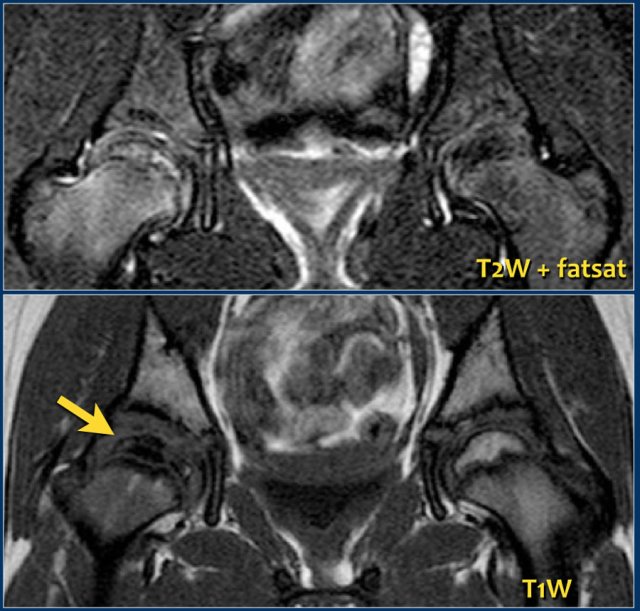

Early on in the disease radiographs may be negative, but MRI will show edema in the femoral head with loss of high bone marrow signal on T1-weighted images.

Sometimes a radiographically occult fracture can be detected on MRI as a double rim sign on T2-weighted images with fatsat.

Joint effusion may be present.

Cartilage may become hypertrophic on the affected side.

The images show right-sided Perthes disease in a nine-year old girl.

There is loss of T1 high signal of the fatty marrow due to edema and sclerosis.